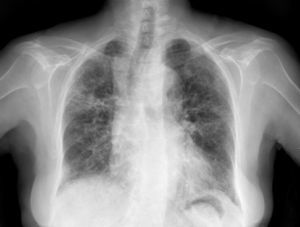

Caso clínicoSe trata de una mujer de 83 años, con antecedentes de hipertensión arterial en tratamiento con amlodipino 5mg/día, enfermedad renal crónica en estadio iii, secundario a nefroangioesclerosis (filtrado glomerular de 45ml/min) y polimialgia reumática en tratamiento crónico con metotrexato 15mg/semanal, desde hace 4 años, aproximadamente. Durante los últimos años ha permanecido con buena estabilidad clínica y analítica, no requiriendo tratamiento corticoideo asociado ni ajustes de su medicación habitual. Seis semanas previas al ingreso presentó de forma progresiva astenia, disnea, tos productiva y pérdida ponderal de 5 kg durante este tiempo. No fiebre termometrada, no artralgias ni debilidad muscular. En el ingreso, se objetivó disnea en reposo con saturación de oxigeno basal del 90%, auscultación pulmonar con crepitantes finos bilaterales, no adenomegalias ni visceromegalias palpables, elevación de la velocidad de sedimentación globular de 69mm, proteína C reactiva de 3,5mg/dl y radiografía de tórax, donde destacó un infiltrado reticular bilateral difuso y asimétrico con afectación periférica, más acentuado en las bases y en el lóbulo superior derecho (fig. 1). Tras realizar un diagnóstico diferencial de neumopatía subaguda en el contexto de la paciente, la sospecha de neumopatía por metotrexato fue el principal planteamiento, por lo que se suspendió dicho tratamiento, se inició corticoterapia por vía intravenosa de 48mg/día de metilprednisolona y medidas de soporte, a pesar de lo cual no se objetivó clara mejoría. Se realizó una tomografía axial computarizada de alta resolución (TACAR) torácico, objetivándose un engrosamiento intersticial parcheado de predominio periférico y en las bases pulmonares, así como pequeñas adenopatías mediastínicas inespecíficas (fig. 2). Las pruebas de función respiratoria mostraron una espirometría forzada con valores en el límite bajo de la normalidad, con una capacidad vital forzada (FVC) de 1.340ml (82%), un volumen de flujo espiratorio en el primer segundo (FEV1) de 1.130ml (88%) y el cociente FEV1/FVC del 84%, asociado a un descenso grave de la difusión pulmonar de monóxido de carbono (DLCO) del 33% y corregido según el volumen alveolar (KCO) del 54%. En el resto de las pruebas complementarias, no se evidenciaron alteraciones en el hemograma, la serología para gérmenes atípicos, el estudio de marcadores tumorales, los hemocultivos, el estudio seriado de esputo ni en el Mantoux/Booster, por lo que se realizó una broncoscopia con estudio del lavado broncoalveolar (LBA) y broncoaspirado, obteniéndose resultado positivo en la reacción en cadena de la polimerasa (PCR) para CMV asociado a un incremento del índice de linfocitos CD4/CD8 de 3.47, con el resto de estudio para gérmenes comunes, tuberculosis, Pneumocistis jiroveci y hongos negativo. Se amplió el estudio microbiológico detectándose IgG para CMV (+), IgM para CMV (–) y carga viral CMV en plasma (+), por lo que se inició tratamiento por vía intravenoso, ajustado según función renal, con ganciclovir 300mg/12 h durante 14 días, cambiando posteriormente a valganciclovir 900mg/12 h por vía oral durante 14 días, con buena tolerancia a la medicación y respuesta clínica, mejorando los parámetros radiológicos, serológicos (carga viral CMV indetectable) y de función respiratoria (DLCO 57,52%, KCO 80,90%, FVC 1.950ml [119%] y FEV1 de 1.680ml [130%]).